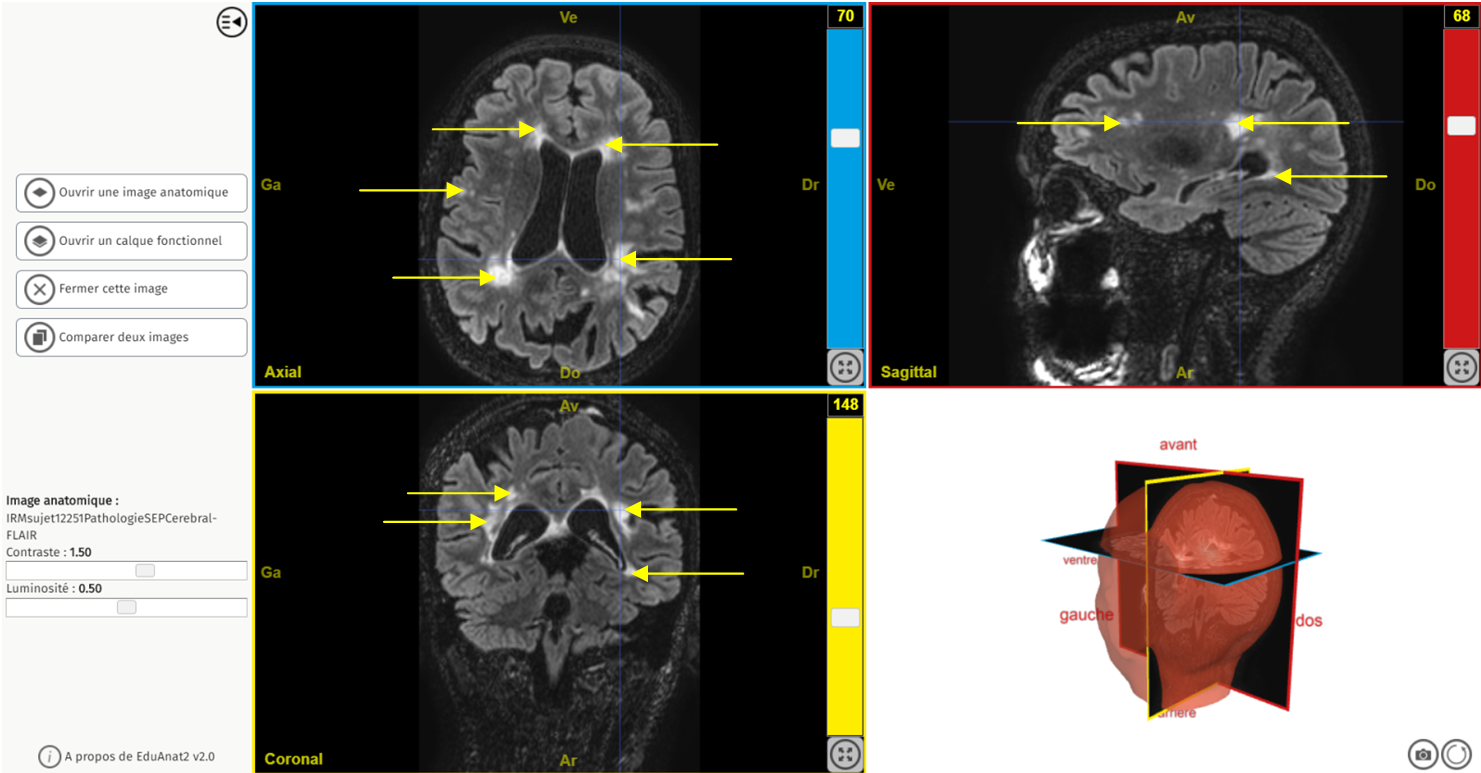

Ancien logiciel : EduAnatomist et Neuropeda

Exemple de lien direct vers EduAnat 2 en ligne